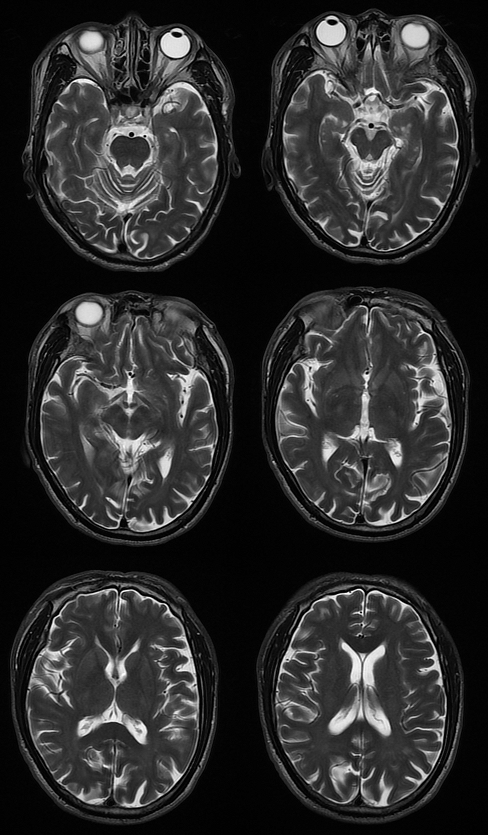

T2

MRI 影像描述:T1W1 可见双侧苍白球对称高信号,T2、T2FLAIR、DWI 相应部位均未见确切异常信号。

普遍接受的 HE 颅脑 MR 常规成像特点为 T1WI 上基底节区尤其是苍白球双侧对称性高信号,其他部位如黑质、中脑被盖以及垂体等也可出现异常高信号;T2WI 上多无明显改变,组织学证实苍白球密度增高是猛沉积的结果。健康人在摄入锰之后可迅速被肝脏清除,并排出人胆道系统。肝硬化病人锰经胆道排泄减慢,导致血锰水平升高及脑中锰聚集增加。因锰离子在第 3 轨道有 5 个不配对电子而具有较大磁矩,能明显缩短 T1 弛豫时间,导致 T1WI 高信号。